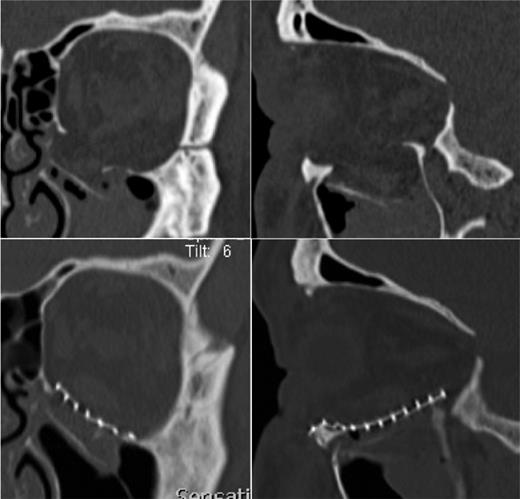

Accordingly, the preoperative CT scan was re-evaluated in 0.5 mm slices and the pre-existence of the ruptured IR was shown (Fig. 3). After ophthalmological consultation and treatment of the patient with a combination of orthoptics and prismatic glasses, satisfactory functional recovery was achieved after 6 months without need of surgical repair of the ruptured muscle.

The preoperative 0.5 mm sliced CT of the orbit presents the tear of the IR muscle in his middle part.